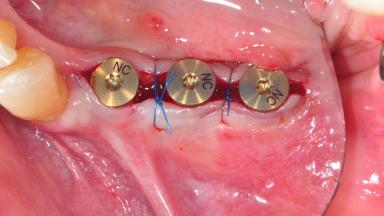

Placement of Narrow Diameter Two-Piece Implants with Simultaneous GBR

Surgical treatment of a 68-year-old female patient with a distal extension situation in the left mandible. As the CBCT analysis reveals, the bone crest anatomy in the area is not ideal and necessitates an augmentation procedure to achieve a good long-term prognosis for the planned implants and their prostheses.

After the placement of three diameter-reduced two-piece implants the bone is augmented with autologous bone chips and DBBM particles to enlarge the crest volume. The surgery is completed with the application of two membrane layers and primary wound closure.

For soft tissue management, the initial healing caps are replaced with a longer type 8 weeks after implant placement in a second intervention before prosthodontic treatment is initiated.